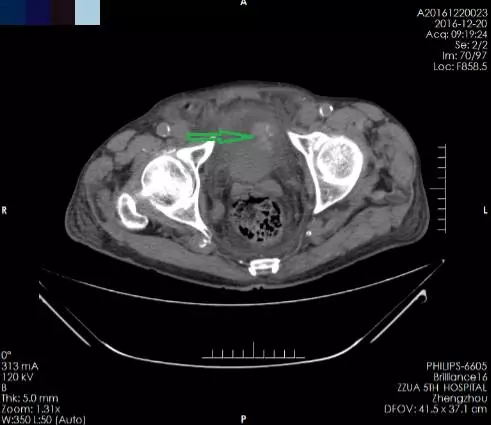

箭头所指为膀胱肿瘤